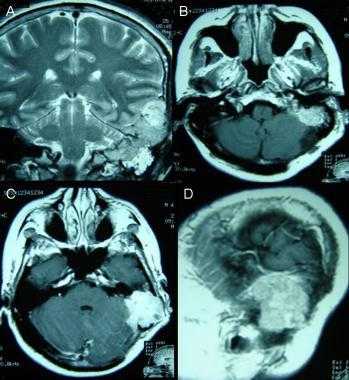

Фалькс-менингиома на МРТ.

А: на Т1-взвешенном МР-изображении отмечается солидное образование, характеризующееся изоинтенсивностью по отношению к твердой мозговой оболочке, инвазией в кость и сдавлением теменных зон коры.

В: На Т1-взвешенном МР-изображении с контрастным усилением видна частично контрастируемая опухоль.

С: На корональном Т2-взвешенном изображении видно изоинтенсивное образование, что соответствует плотной ткани. Такая картина характерна для фибробластных менингиом.

D : На Т1-взвешенном МР-изображении с контрастным усилением визуализируется гиперинтенсивное образование внутри мозгового вещества кости.